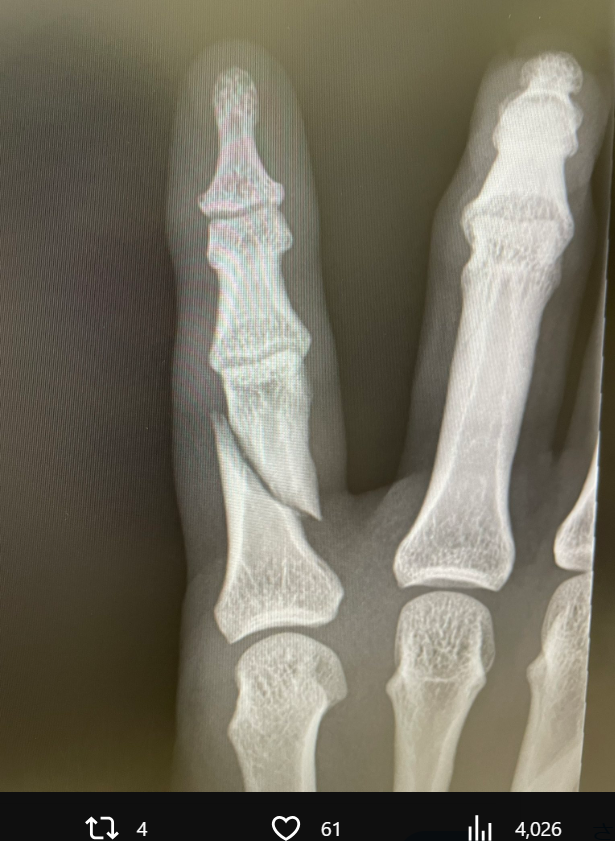

福田の左小指の骨折レントゲン写真(@muaythaikaito)